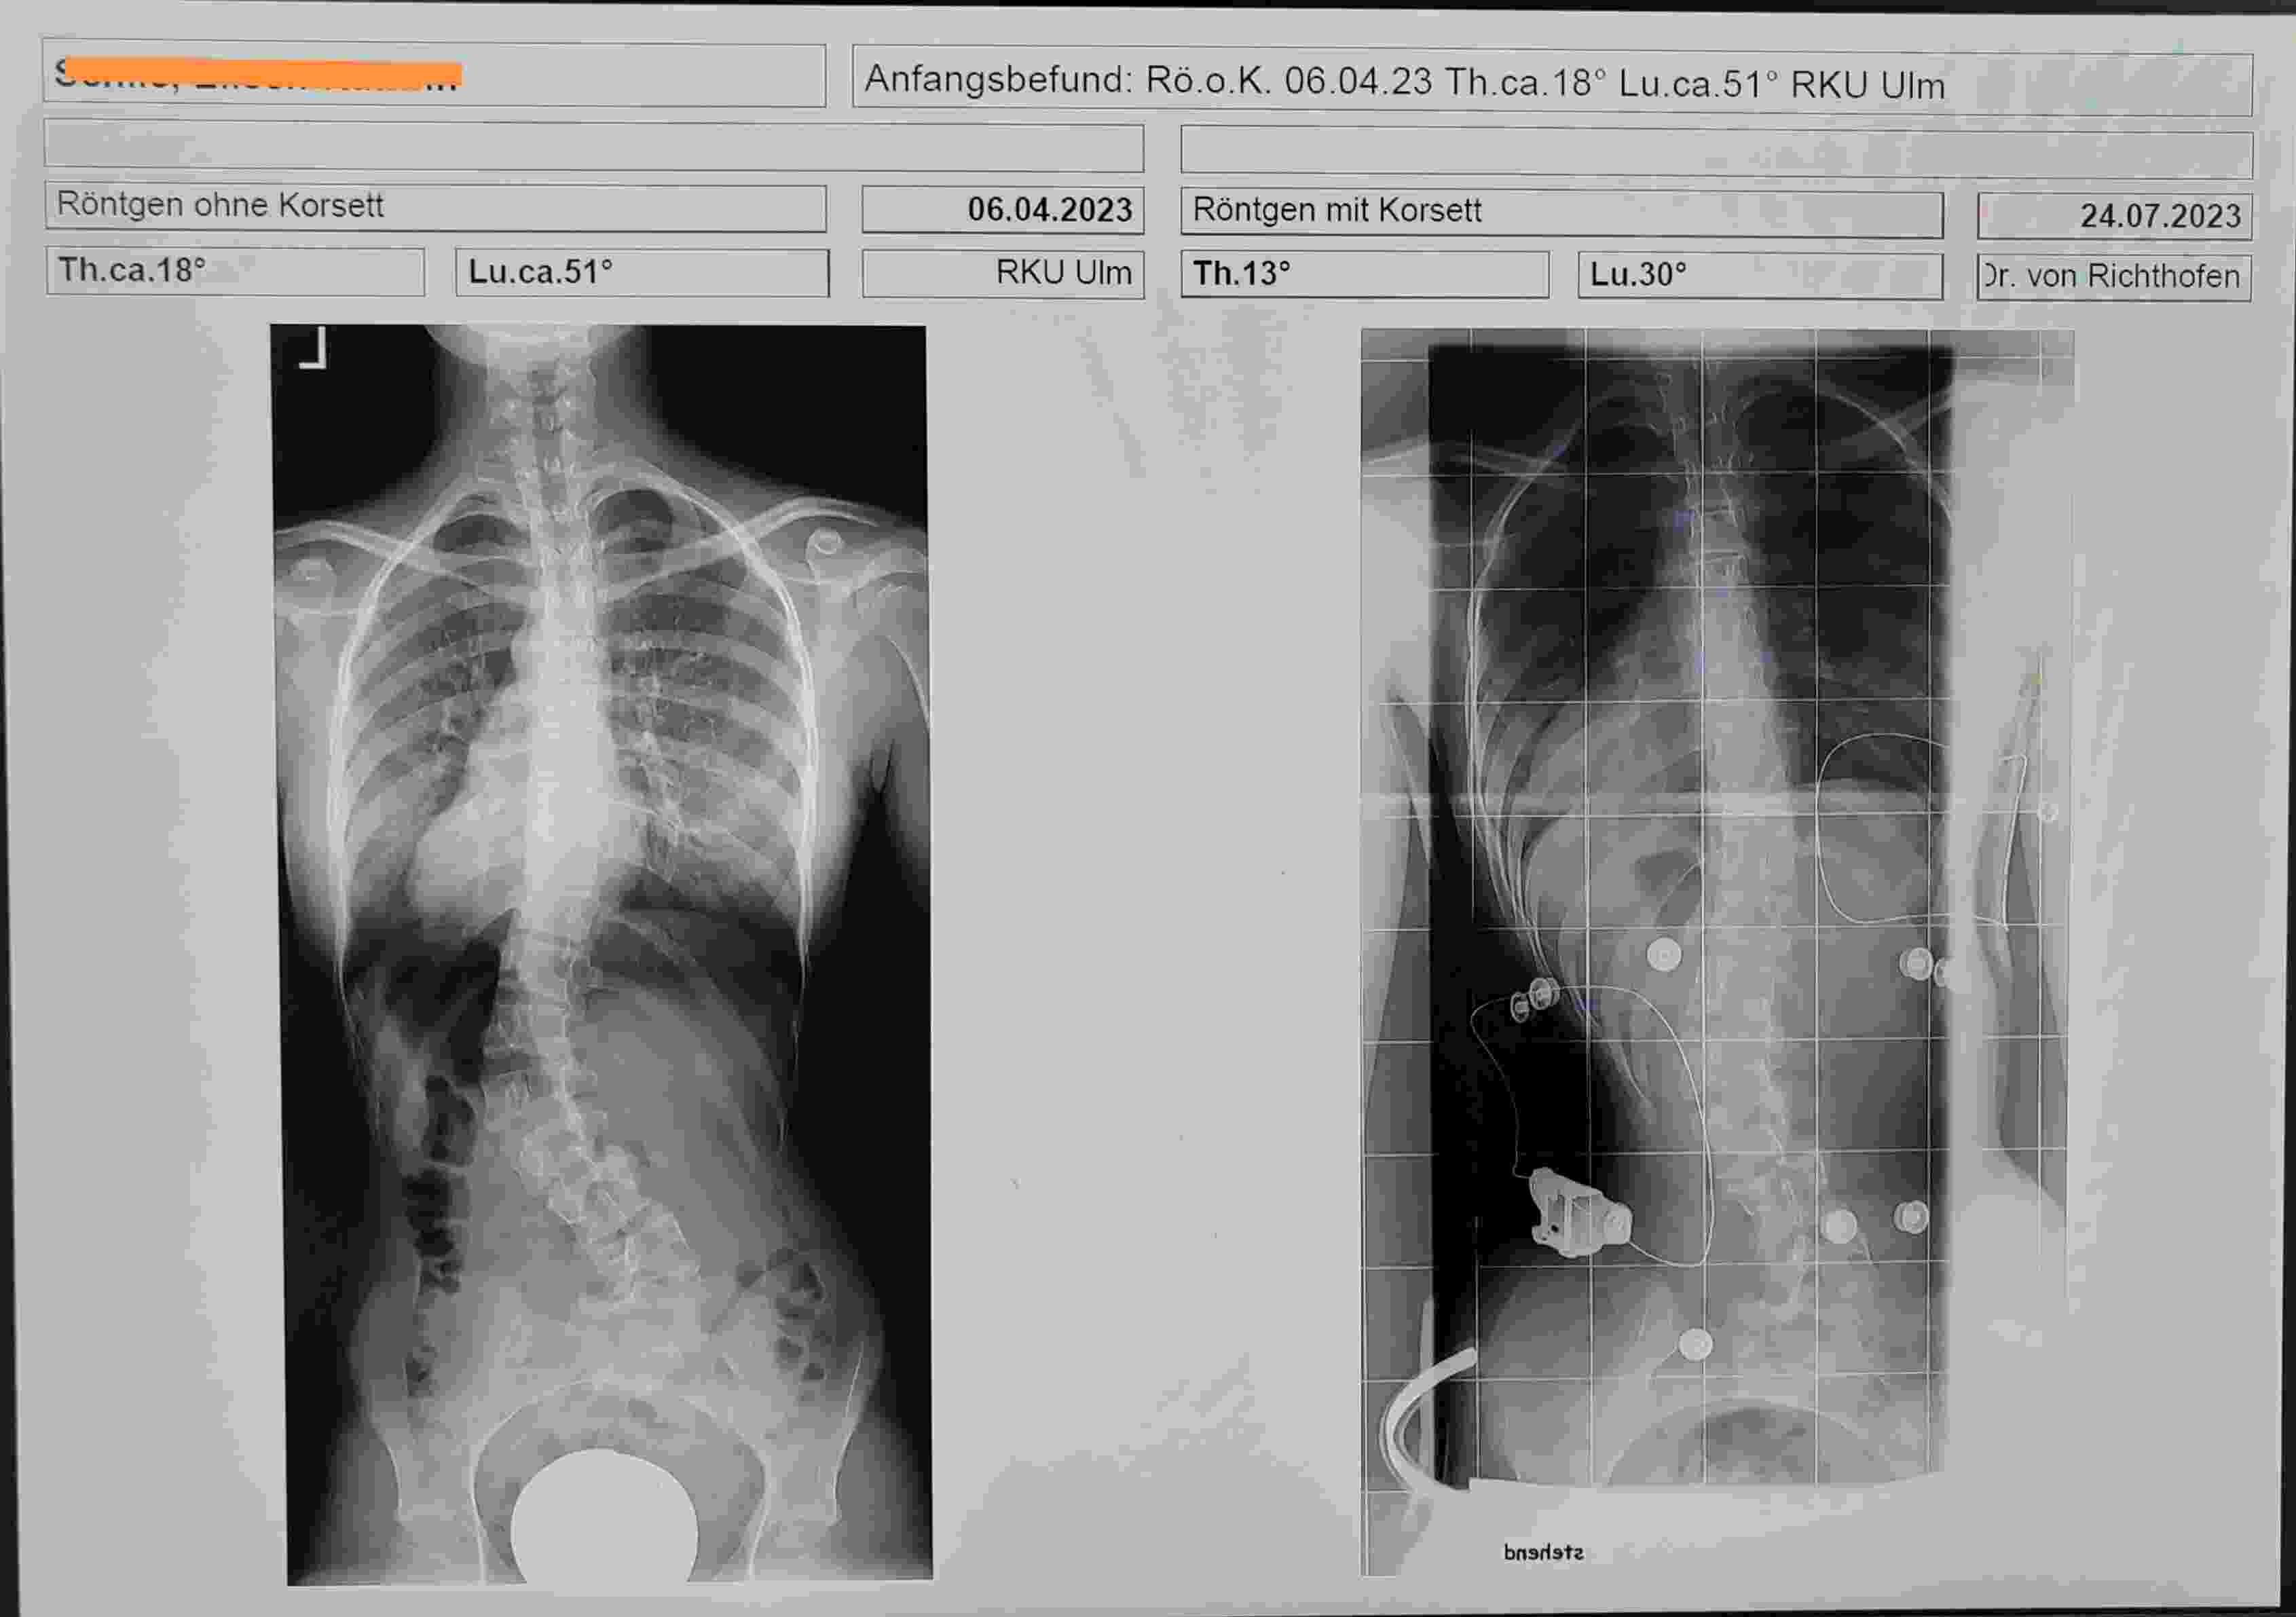

Zuvor hatte meine Tochter Th bei ca. 18° und Lu bei ca. 51° was allerdings beim Röntgenbild ohne Korsett war, da das RKU das letzte aktuelle Röntgenbild ohne Korsett gemacht hat.

Nun liegen die Werte im Korsett bei Th 13° und Lu 30°.

In der grafischen Darstellung des von Dir mitgebrachten Röntgenbildes vom 6.4.23 ist ja auch die Rede von:

thorakal 18° und lumbal 51° (ohne Korsett)

Und dem gegenübergestellt ist das Röntgenbild aus der Praxis von Dr. von Richthofen vom 24.7.23 mit

thorakal 13° und lumbal 30° (mit Korsett)

Also ob im Korsett lumbal nun 35° oder 30° bzw. ohne Korsett 45° oder 51° vorhanden sind, finde ich aufgrund von Meßtoleranzen nicht so relevant.

Das Problem ist hier in der Diskussion die häufige Angabe von Winkeln ohne Bezug. Du hast Dich hauptsächlich auf die lumbale Situation bezogen, weil der thorakale Winkel tatsächlich relativ klein ist. Der hat aber für die Irritation gesorgt, weil die falsche Angabe mit 53° (im Bericht) eine ganz andere Situation vorgegauckelt hatte.

Ein Spezialist, der in eigener Praxis die Patienten über längere Zeit im Behandlungsversuch begleitet, ist schon etwas anderes, als ein Schroth- REHA Arzt. Und dieser Versuch hat doch gerade erst angefangen und ist doch jetzt schon mit einer lumbalen Korrektur von 21° ein guter Erfolg !